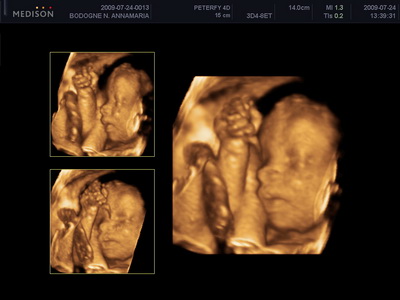

Mi megvagyunk, növögetünk ezerrel. Pénteken voltunk 4d-n, minden rendben van. Lilike most már biztos hogy Lilike, nem szégyenlős a drágám, rendesen bepucsított és szép kis hurija is van. 1000g-nak mérték és azt mondta a doktornő, hogy készüljünk, hogy szép nagy baba lesz. Nem a súlya lesz óriási, hanem szép hosszú lesz, lehet hogy 58-60 cm :lol: Mondjuk erre számítottunk mert mi se vagyunk alacsonyak :lol: Egyébként tiszta apja a kis drága. Nagy csókos szája van és kis kerek arcocskája. Teljesen beleszerettem :lol: Még puszit is küldött nekünk a kis husi szájával. Teszek fel pár képet nektek.

Kép

Kis csókos szájú

Vitathatatlan nunis

Nyitott szemmel